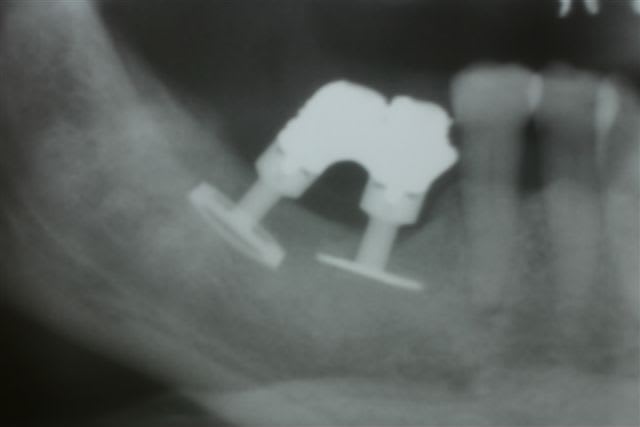

Le cas 2 c est pour plus tard car un peu plus long à expliquer mais là ça commençait par un échec de greffe avec de l iliaque pour remplacer 47 46...

La praticien de la patiente pose ds une greffe molle 3 cylindres et en garde un seul , le mésial et comme par hasard celui qui ds son os natif et pas ds le greffon

Je lui ai posé une première fois une plaque sans ostéotension car cela n existait pas à l époque... Mierda la plaque s expose en lingual et je dois me résoudre à la dépose :-(

Je laisse le site au repos et je viens qques moins plus y reposer un monodisk 8G2DM7 avec apport de nanobone et prfs... Encore mierda il se mobilise et se fibrose

Entre temps je lui fais 3 séances d ostéotension manuelle qui rend le site un plus vascularisé et donc pus exploitable... Je me décide à déposer ce disk en vue simplement de refermer le site sur un nouvel apport de nanobone et là lors de la dépose le site m inspire : bien sanglant et très belle os corticalisé sous le disk : je me jette ds la bagarre et je repose de suite un 9G2DM que je peux bien bolquer avec une vis d ostéosynthèse en vestibulaire ds cette belle corticale sous le disk. Nanobone + PRF + Membrane de Jason...et laissé en enfoui qques mois

Au bout de ces qques mois prise d empreinte sur un disk sonore comme un cylindre et totalement fixe sans l ombre d une sensibilité

Evidemment cette patiente m a tjs posé bcp de question mais je lui avais posé au maxillaire une plaque et un disk qui s étaient intégrés sans aucun ennui donc elle savait que seule de mauvaises circonstances nous avaient empêché de réussir ds le secteur 40

Entre la greffe et mon dernier disk 7 ans sont passés mais je pense que c est effectivement le fait d intervenir plusieurs fois en dépériostant et donc en dévascularisant le site qui nous fait aller ds le mur... En fait j ai laissé de long tps morts pour que l os récupère et j ai choisi de réimplanter de suite lors de la dernière dépose pour éviter encore une meurtrissure supplémentaire pour ce site par un n-ième passage chirurgical à cet endroit